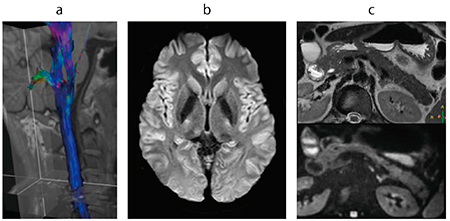

図6 TSE DWIによる真珠腫例(←:腫瘍,←:液貯留)

a:T2W/TSE,slice thickness:3mm

b:TSE DWI,slice thickness:3mm

c:dS Zoom TSE DWIとT2W Fusion,FOV:50mm×80mm,slice thickness:1.5mm

(画像ご提供:東北大学病院様)